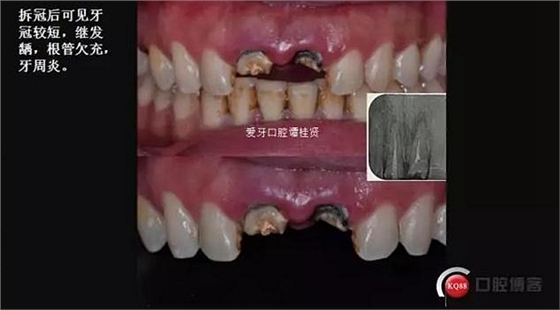

口內(nèi)檢查:很輕易就取下牙冠,均為殘冠殘根且繼發(fā)齲,#21尤為嚴(yán)重,已到齦下,牙周探診1.5mm,X線檢查:根尖陰影,欠充。

診斷:#11#21殘根,繼發(fā)齲,輕度牙周炎。

三診 牙周牙髓聯(lián)合治療